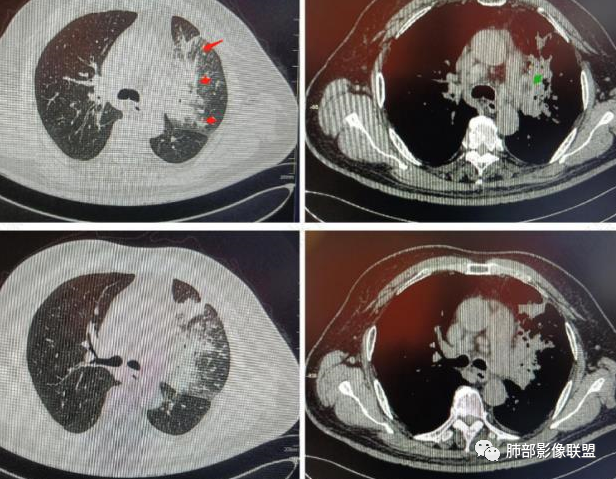

图1、2为同一病例,左肺下叶背段周围型肺Ca并左肺下叶局限型PLC,肿块与左下肺门间肺纹理不规则增粗,肿块与膈面有串珠样高密度影相连。图3为乳腺癌化疗后多发转移并弥漫型PLC,双肺多肺叶肺纹理不规则增粗增多并多发微小结节,其中右肺上叶后段肺纹理多呈典型的“毛刷征”,双肺上叶胸膜下区可见多发垂直于胸膜的不规则增厚的小叶间隔及微小结节。图4为右肺上叶周围型肺癌并弥漫型PLC,左肺上叶背段肺纹理不规则增粗增多呈典型的“毛刷征”,右侧叶间胸膜轻度增厚及多发微小结节。图5为胰腺癌术后多发转移并弥漫型PLC,双肺广泛肺纹理增多增粗并多发微小结节,双肺胸膜下多发肺小叶间隔增厚并见微小结节;图6(MPR冠状位)为食管癌术后肺弥漫型PLC,左肺广泛肺纹理不规则增多、增粗及多发小结节,边缘模糊。